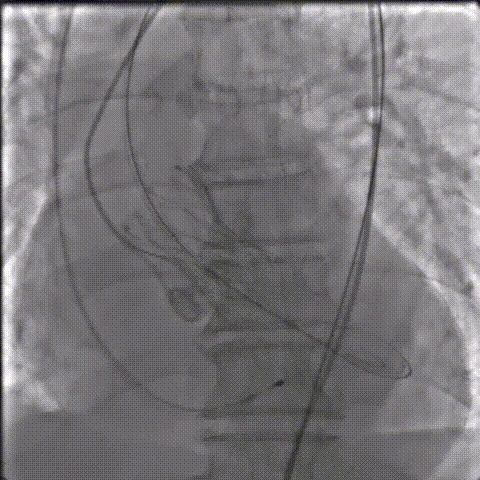

手术影像记录

主动脉根部造影

18mm球囊预扩

AV26瓣膜工作位造影

缓慢脱钩